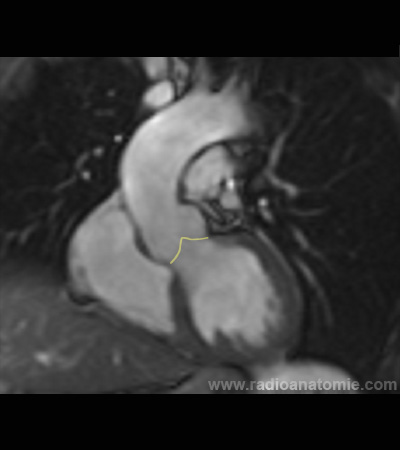

Chambre de chasse du ventricule gauche LVOT2

Plan valve aortique

Plan chambre de chasse du ventricule gauche (LVOT)

Valve aortique

Muscles papillaires

Ventricule gauche

Ventricule droit

Oreillette droite

Aorte ascendante

Artère pulmonaire

Septum interventriculaire